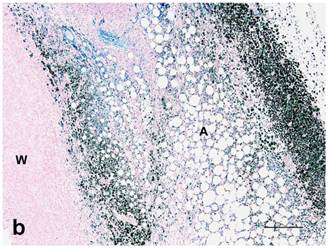

Figure 5

(a): Center of treated tumor demonstrating cytoplasmic and nuclear iron staining (seen as blue or green) in necrotic epithelium (E) and extracellular iron (arrow). Perl's iron stain. Bar= 100 microns; (b): Extensive iron staining (seen as blue or green) around a tumor that is cytoplasmic in macrophages, fibroblasts, and adipose tissue (A). Tumor wall (W) does not have any iron staining. Perl's iron stain. Bar= 200 microns.

Both treated and nontreated tumors were composed of one or more circumscribed nodules that had a peripheral wall of neoplastic stratified squamous epithelium, which differentiated centripetally, and central necrosis. Treated tumors had variable degrees of ulceration and inflammation of the tumor wall as compared to the nontreated control tumors that had none (Figure 4). Remaining epithelium in the wall of treated tumors was mostly viable, but coagulative necrosis was present in one. Treated tumors also had more severe inflammation around the tumor and within the wall and centers of the tumors than the nontreated controls. No stainable iron was observed in the nontreated controls. However, the treated tumors had abundant iron which was free and intracellular (cytoplasmic and nuclear) in the tumor centers, rarely in the cytoplasm and nuclei of the wall, and then only in necrotic cells, and around the tumors as extracellular lakes and cytoplasmic in macrophages, fibroblasts and adipocytes (Figure 5). Caspase 3 staining was similar between the treated and nontreated tumors, with staining of multiple small groups of epithelial cells and inflammatory cells at the interface between the wall epithelium and in the central area of necrosis (Figure 6).